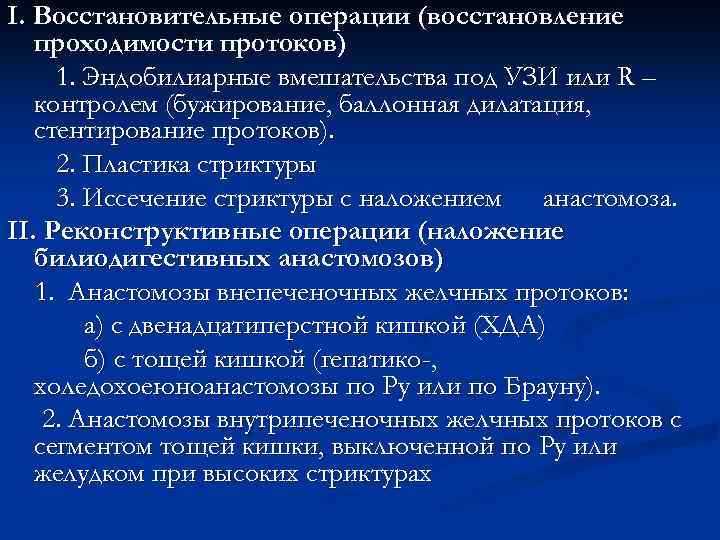

I. Восстановительные операции (восстановление проходимости протоков) 1. Эндобилиарные вмешательства под УЗИ или R – контролем (бужирование, баллонная дилатация, стентирование протоков). 2. Пластика стриктуры 3. Иссечение стриктуры с наложением анастомоза. II. Реконструктивные операции (наложение билиодигестивных анастомозов) 1. Анастомозы внепеченочных желчных протоков: а) с двенадцатиперстной кишкой (ХДА) б) с тощей кишкой (гепатико-, холедохоеюноанастомозы по Ру или по Брауну). 2. Анастомозы внутрипеченочных желчных протоков с сегментом тощей кишки, выключенной по Ру или желудком при высоких стриктурах

I. Восстановительные операции (восстановление проходимости протоков) 1. Эндобилиарные вмешательства под УЗИ или R – контролем (бужирование, баллонная дилатация, стентирование протоков). 2. Пластика стриктуры 3. Иссечение стриктуры с наложением анастомоза. II. Реконструктивные операции (наложение билиодигестивных анастомозов) 1. Анастомозы внепеченочных желчных протоков: а) с двенадцатиперстной кишкой (ХДА) б) с тощей кишкой (гепатико-, холедохоеюноанастомозы по Ру или по Брауну). 2. Анастомозы внутрипеченочных желчных протоков с сегментом тощей кишки, выключенной по Ру или желудком при высоких стриктурах